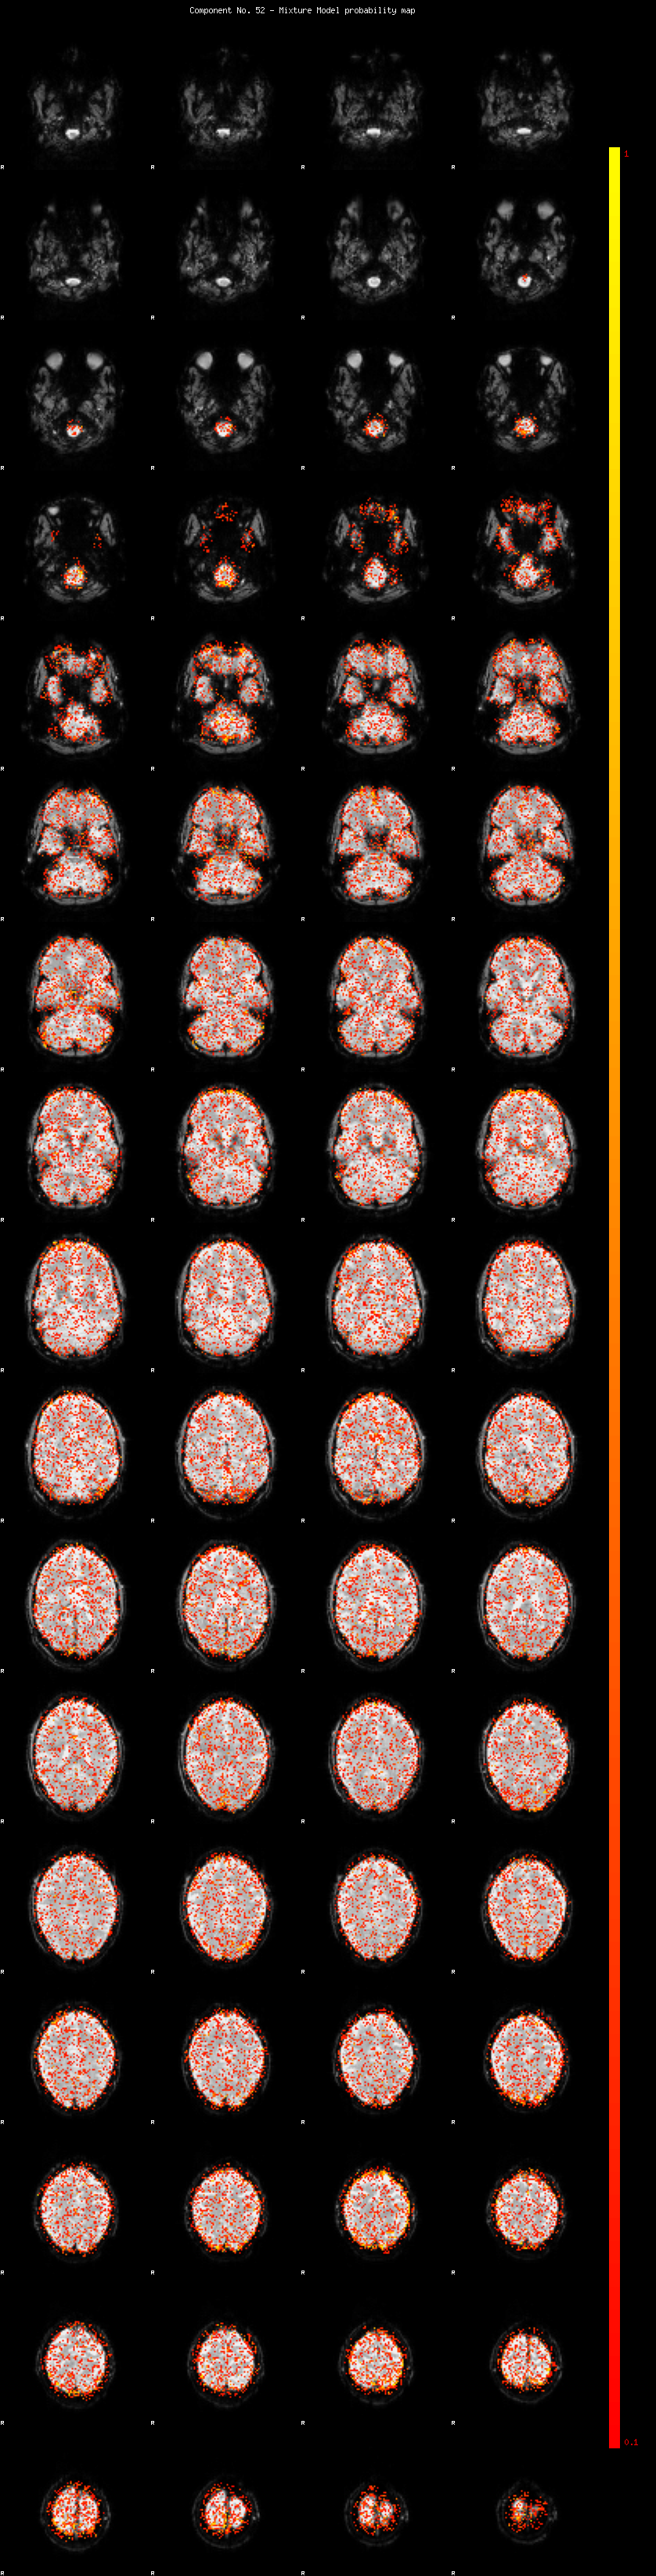

IC_52 Mixture Model fit

Means : 0.000000 1.988712 -1.997895

Vars : 1.000000 0.620459 0.637299

Prop. : 0.922235 0.037232 0.040532